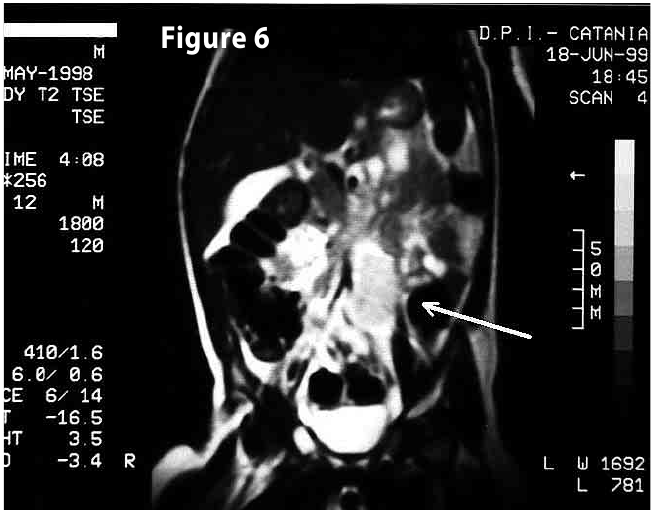

Figure6

Figure6-7